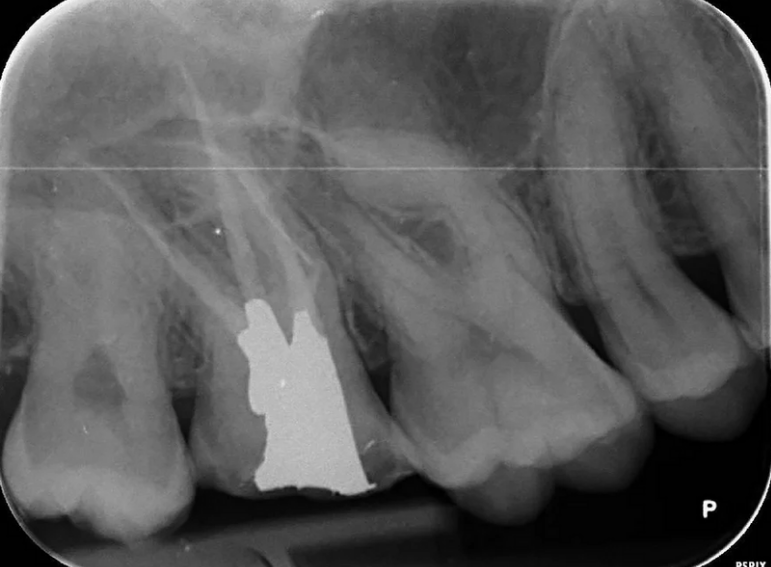

Separated instrument management on a sclerosed upper second molar.